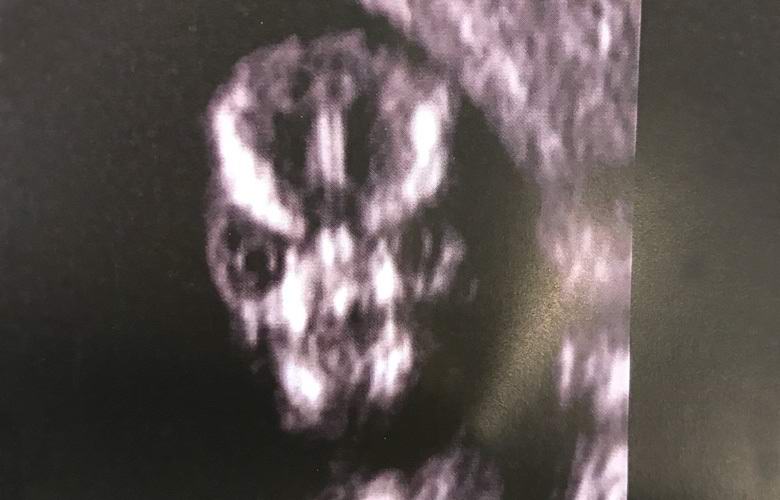

Nosečnica Sharney Turner je obiskala bolnišnico za sonografija ploda in na zaslonu ultrazvočnega aparata opazil goreč obraz, ki jo spominja bodisi na grozljivo pošast, bodisi na tujec od drugega planet.

Bodoča mati je zdravnike takoj vprašala, kakšna groza. Zdravniki pa so žensko pomirili in ji rekli, da je lobanja ima otrok lahko med pregledovanjem takšen videz in ni razloga za skrb.

Specialist za ultrazvok se odloči za skeniranje obraza moj fant in izkazalo se je, da sem najbolj grozljiva stvar kar sem jih kdaj videl v življenju. Je to res človeško ali lobanja izgleda pod ultrazvokom? Zanimivo je, da je vedno tako strašljivo ali je samo moj dojenček tako grozen?